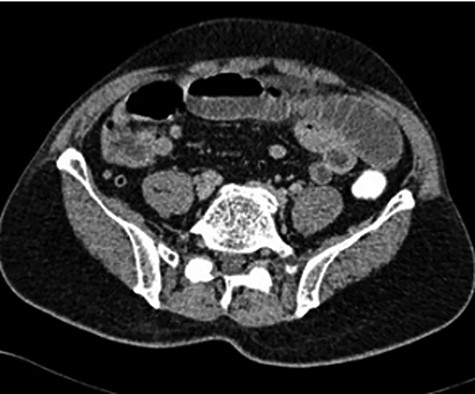

After 5 days, a 61-year-old Indian gentleman presented with generalized abdominal pain and vomiting for 5 days. On examination, his abdomen was distended, but soft and non-tender. CT abdomen revealed dilated small bowel with a suspicious mass at the ileum (Fig. 4). He denied neither swallowing any foreign body nor mushroom. Nasogastric decompression was done, but his condition did not improve with conservative measures. He underwent exploratory laparotomy where an intraluminal mass was found 160 cm from the terminal ileum with collapsed bowel distally. An enterotomy was done and an uncut mushroom was found (Fig. 5). Later on, he recalled that he had indeed consumed a piece of Chinese mushroom 7 days prior to admission.

CT scan showing a suspicious mass at the distal ileum of the second patient.